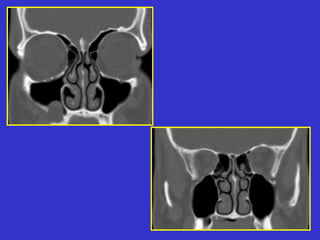

Este documento describe las diferentes proyecciones radiográficas utilizadas para examinar los senos paranasales, incluyendo las proyecciones básicas de Caldwell, Waters lateral y las proyecciones especiales como Hirtz y Waters mentonasal. También describe las diferentes estructuras anatómicas que componen el complejo ostiomeatal anterior y posterior de los senos paranasales.